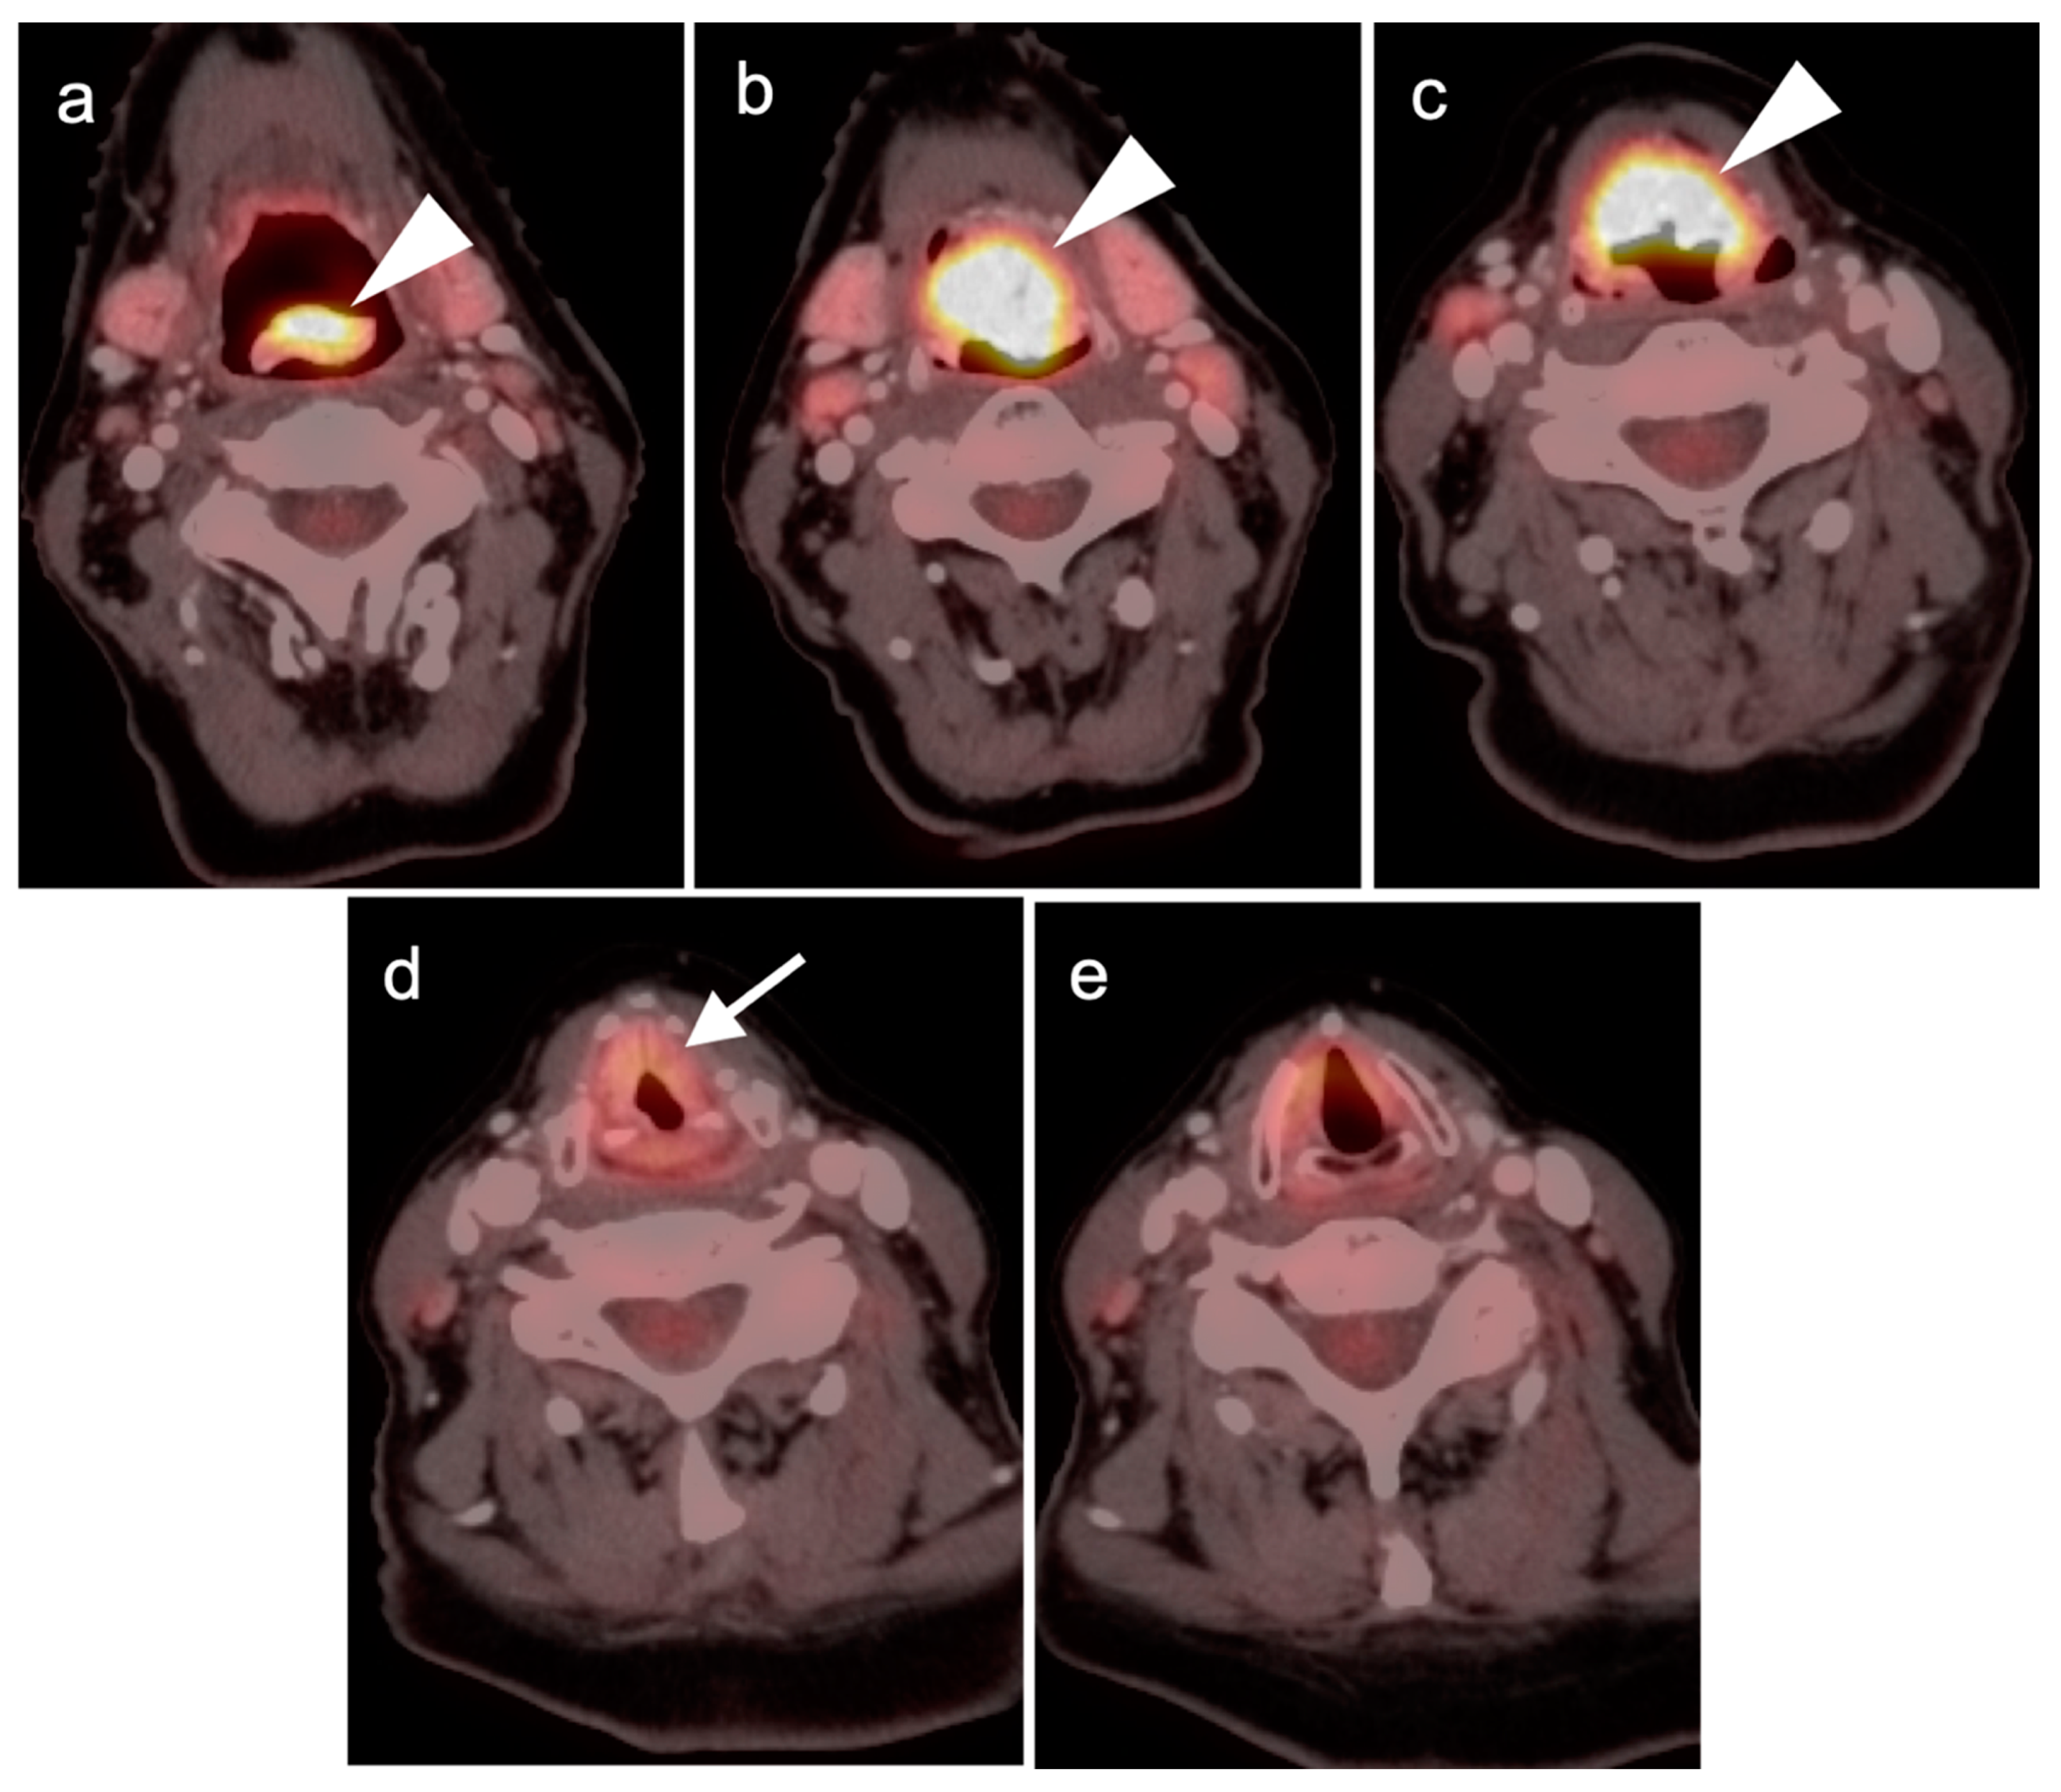

2.2. Squamous Cell Carcinoma of the Head and Neck (SCCHN)

- Laryngeal squamous cell carcinoma

- a.

- Supraglottic larynx

- b.

- Glottic larynx

- c.

- Subglottic larynx